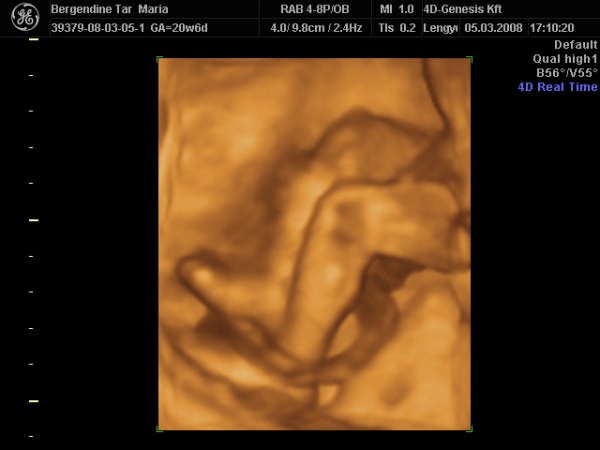

Én azon lepődtem meg, hogy már nem igazán tudjuk egészben látni a törpéket, mert nem férnek rá a monitorra

Nem mintha nem lenne tök klassz, hogy már ilyen nagyok!